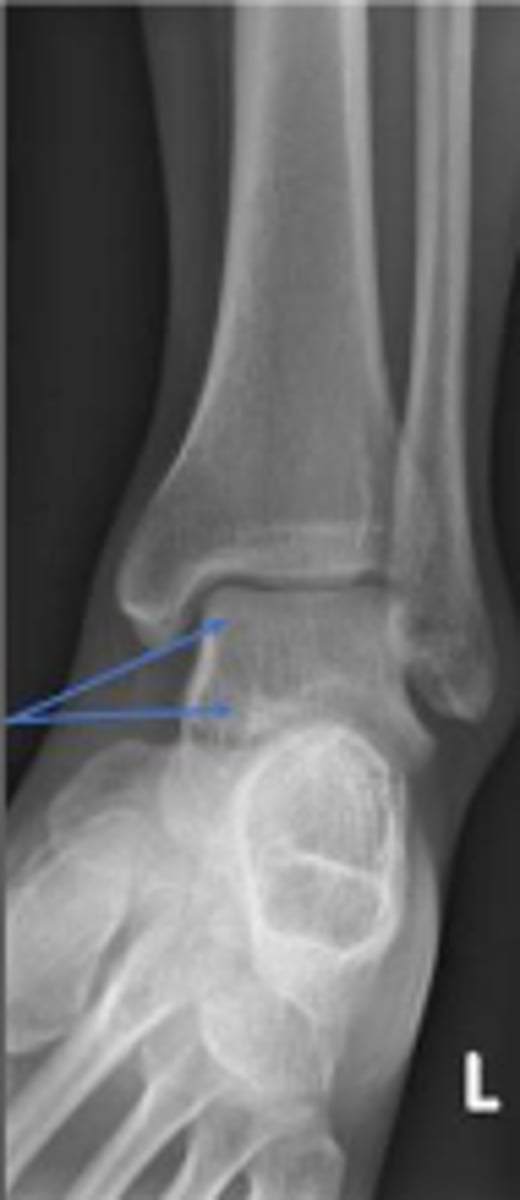

Left AP ankle

What is the name of the radiographic view?

Axial relationship of the ankle

What is the overarching name of the assessment?

Tibial angle & fibular angle

What are the 2 components of the assessment?

Tibial angle

What is the name of the assessment?

Yes

Is the assessment within normal limits?

Fibular angle